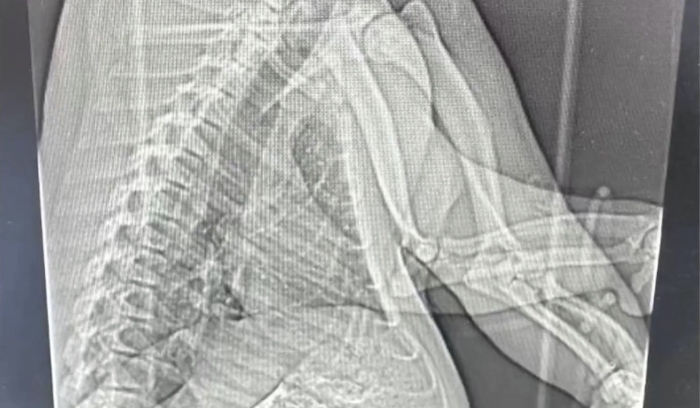

▲大熊猫“七七”照胸腹部 CT 。 网上图片

“七七”于27日被送到上海仁济医院照胸腹部CT,报告证实是肠梗阻。园方对记者表示,专家组已决定为“七七”施手术。